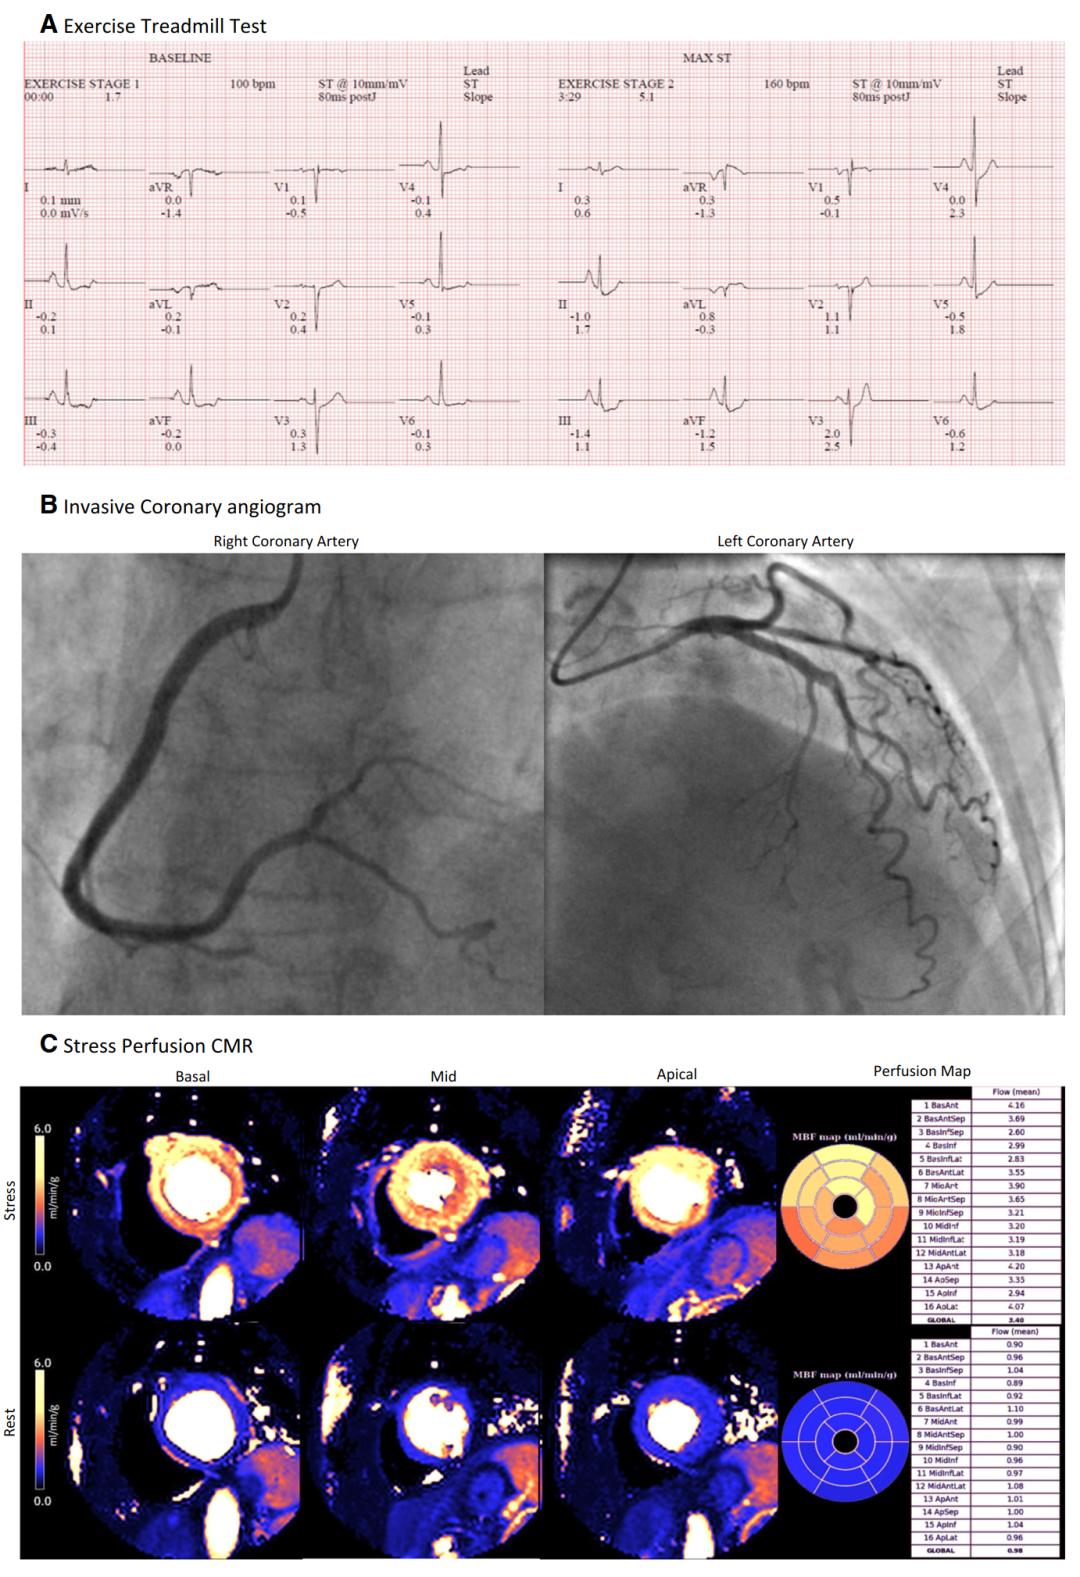

图2 66岁女性,因胸痛被转到心脏科门诊,进行多模式检查。A运动心电图试验没有结果,伴有轻微的ST段抬高,无症状。B侵入性冠状动脉造影显示平滑无阻塞的冠状动脉。C 1.5 T的负荷/静息灌注CMR加上心肌血流的inline像素映射显示正常心肌灌注,负荷MBF正常(全局负荷MBF=3.40 mL·min−1·g−1) 和MPR正常(全局MPR=3.47)。最终诊断为非心源性胸痛。